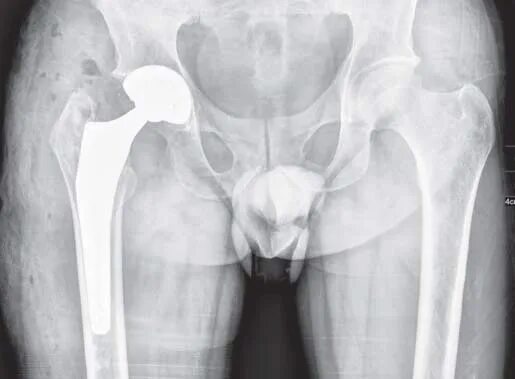

Эндопротез тазобедренного сустава мкб 10